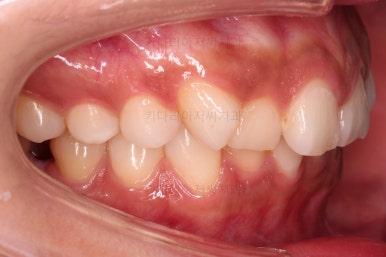

1. 초진

연산동교정치과 초진 시 입안의 모습입니다.

얼핏 앞에서 봤을 때 치열이 나쁘지 않아 보이는데요.

대신 자세히 살펴보면 윗니 양쪽 송곳니가 덧니처럼 볼록 튀어나와 있고요.

아랫니 어금니가 하나 없어서 주위 치아들이 해당 위치로 쓰러진 상태였습니다.

그리고 양쪽의 교합이 톱니바퀴처럼 맞물려 있는 것 같지만 톱니바퀴가 한 칸씩 밀려서 맞물려 있는 부정교합이 있는 상태였습니다.